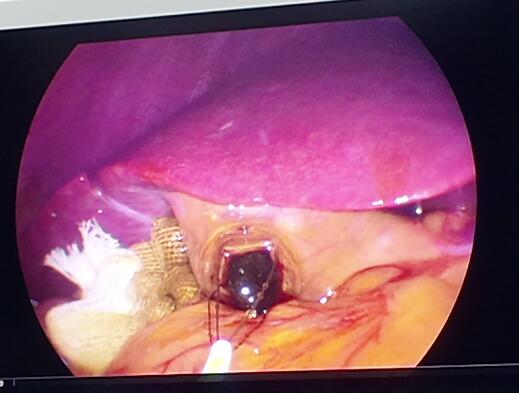

△腹腔镜下,结石正在被取出

手术非常顺利,张智勇副主任通过脐部一个隐蔽的小切口,成功为彭女士取出了一颗黄褐色结石,大小约0.8×1.0厘米。术后,彭女士疼痛感很轻,当天就能下床活动,恢复速度也远超她的预期。